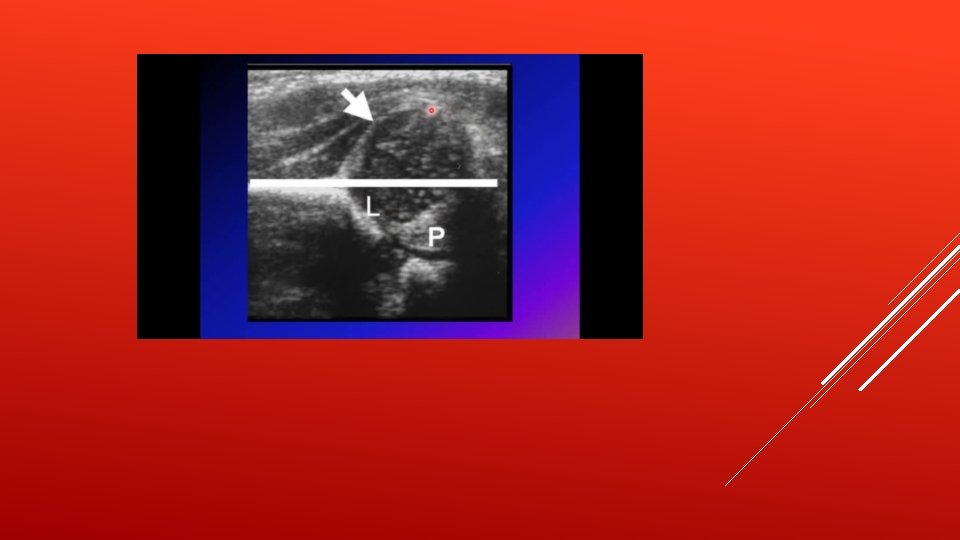

PEDIATRIC HIP - The hip is a deep seated joint and it’s the largest ball and socket joint formed by the acetabulum and femur head. - The acetabulum is the cup-shaped socket on the lateral aspect of the pelvis and it is formed by the ilium, ischium and pubis. - The margin of the acetabulum is deficient inferiorly. An additional fibrocartilaginous margin of the acetabulum is referred to as the acetabular labrum. The labrum functions to deepen the acetabulum, thus holding the femoral head more securely. - At birth the femoral head is less than 50% covered by the acetabulum, and the acetabulum is at its most shallowness and most laxity in order to maximize the hip ROM(range of motion) - After several weeks, the acetabular cartilage starts to develop faster than the femoral head, which allows for more coverage in a normal hip, the ball of the femur fits firmly into the socket - Hip develops after 12 wks of gestation

● Pathology: a. The acetabulum is shallow (shaped like a saucer instead of a cup). b. The femoral head gets dislocated. c. The capsule is stretched and the ligamentum teres becomes elongated and hypertrophied. ● Classification: a. Dysplasia b. Subluxation – Incomplete contact between the articular surfaces of the femoral head and acetabulum. c. Dislocation – Complete loss of contact. d. Instability – Ability to subluxate or dislocate the hip with passive manipulation e. In other words ■ Type 1 → acetabular dysplasia ■ Type 2 → acetabular dysplasia +Subluxation ■ Type 3 → frank dislocation